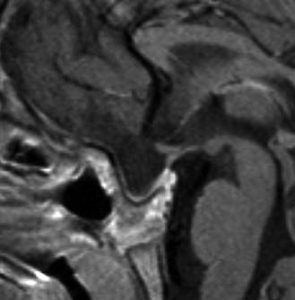

矢印の先に見えるように下垂体は正常の形態です。この画像から灰白隆起の左後方,乳頭体の前方が腫瘍発生母地ということがわかります。尿崩症もなく下垂体機能は正常です。経鼻的な内視鏡手術で腫瘍の大部分を摘出すれば下垂体機能は廃絶します。

とにかく失明を避けるために急いで経蝶形骨洞手術(transsphenoidal-transtuberculum sellae approach)で腫瘍のう胞の減圧をしました(緑の矢印の経路 by 函館中央病院加藤功先生)。その後に前頭開頭で腫瘍を全摘出しました(右側の画像)。尿崩症はでましたが下垂体前葉機能は正常です。

右視力 0.45,左明暗弁の視力が残りました。でももし,経鼻手術をしないでいきなり開頭すればおそらく全盲になっていた例です。